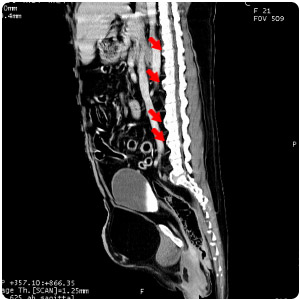

| 脊椎壓迫 transverse |

脊椎壓迫 sagittal |